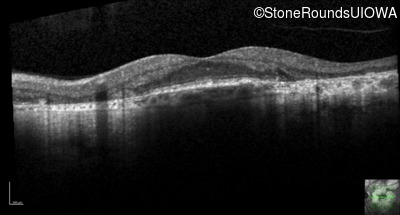

AR Stargardt Disease (IIA)

Age at visit: 51 years

This 51 year old woman first experienced some abnormality in her distance vision when she was 27 years old. She feels that her vision has been stable since that time.

Diagnosis & molecular findings

Disease Gene Allele 1 variant(s) Allele 2 variant(s) Inheritance mode

AR Stargardt Disease ABCA4 Gly1507Arg GGG>AGG IVS42+1 G>A AR